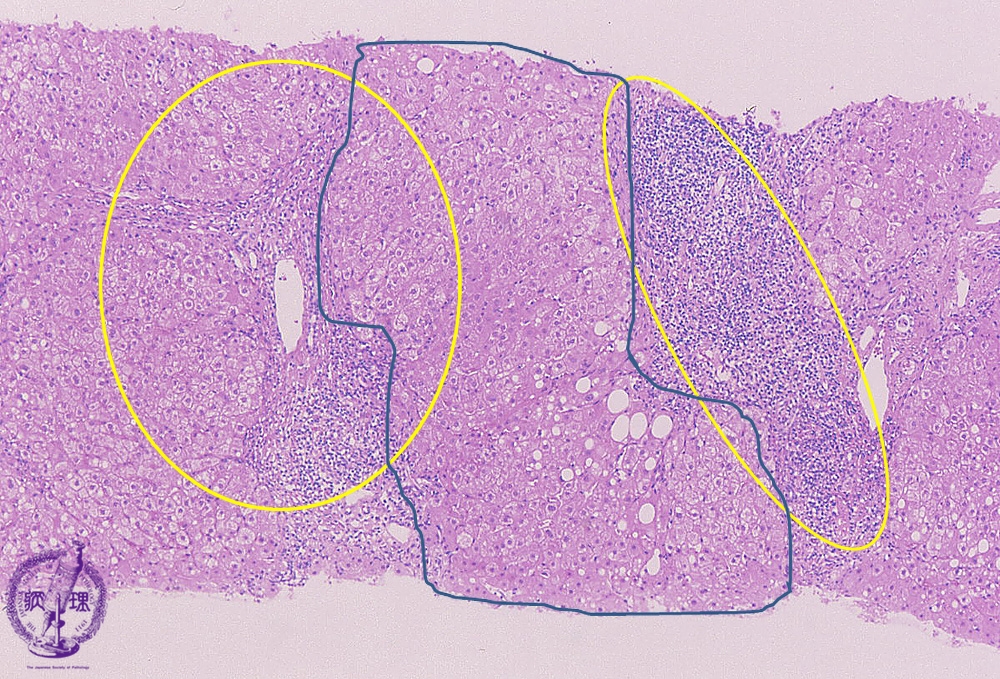

Microscopic image (HE stain, low power view): There is a dense lymphocytic infiltrate with corresponding moderate to marked portal expansion (yellow circle). Fibrosis (blue line) is also seen, and results in disruption of the lobular architecture with segregation of lobules which imparts a nodular appearance in some areas (blue area).